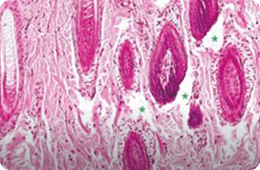

1064 PS

침투깊이 : 499.98~935.23 μm

침투깊이 : 257.12~287.38 μm

출처 : Effect of fractional picosecond laser therapy using a diffractive optical lens on histological tissue reaction, Journal of cosmetic and laser therapy, 2024